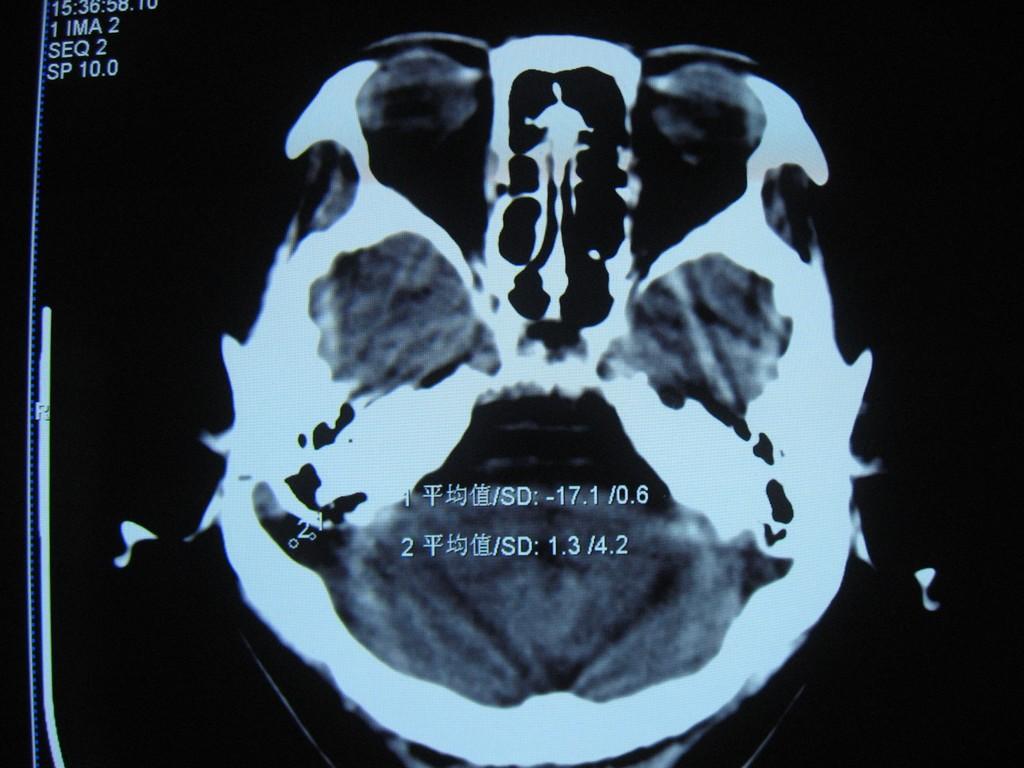

中老年女性病人,头晕头疼做ct,发现右侧乙状窦路径上低密度影,邻近颅骨变薄,ct值见图像上标注,我考虑:1、表皮样囊肿或蛛网膜囊肿。2、乙状窦变异。请问对吗?  乳突导静脉没有考虑,主要是因为向颅底层面扫了几层没有发现右侧颞枕骨骨质完整,没有发现导静脉压迹,欢迎讨论。

1)右侧乙状窦前移。2)右侧乙状窦区皮样囊肿或表皮样囊肿待排;建议行mri检查。

右侧乙状窦前移。2)右侧乙状窦区皮样囊肿或表皮样囊肿